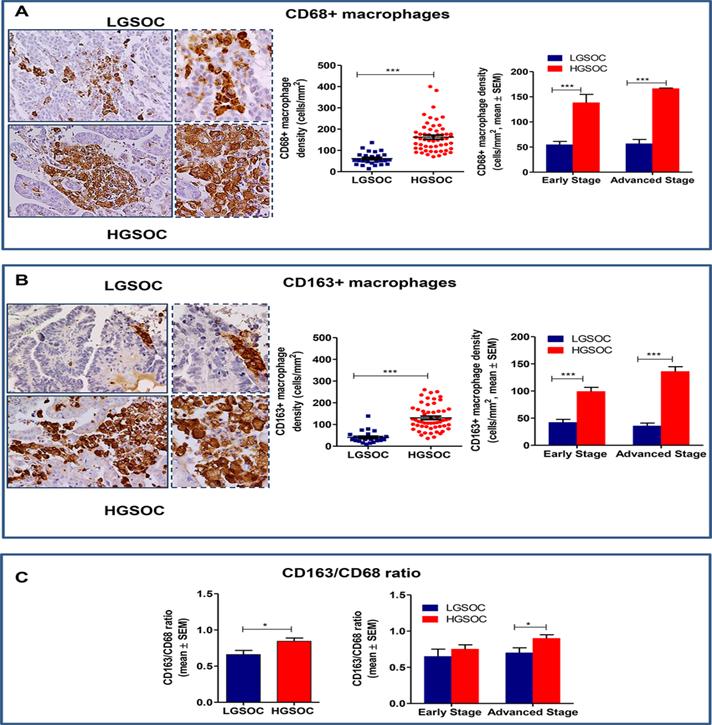

ჰისტომოფოლოგია

LGSOC ჰისტოლოგურად წარმოდგენილია მონოტონური, კუბური მცირედ ეოზინოფილური უჯრედების სახით, ატიპია მერყეობს მუბუქიდან-საშუალომდე,ხოლო მიტოზების რაოდენობა არ აღემატება 12 მიტოზს 10 HPF(მაღალი გამადიდებელი) ველის ფარგლებში – რაც დაბალი პროლიფერაციული აქტივობის მაჩვენებელია.

აღსანიშნავია ის ფაქტი, რომ LGSOC ის სიმპტომები თავს იჩენს შორსწასული ფორმების დროს, განსვავებით HGSOC-გან, შესაბამისად დიაგნოსტირებული შემთხვევების უდიდეს ნაწილში LGSOC-ის გვიანი სტადიები გვხვდება ხოლო HGSOC-ის ადრეული სტადიები.